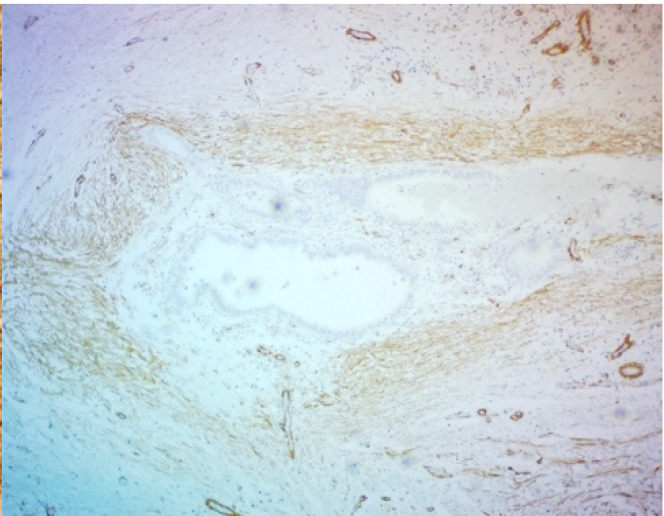

При гистологическом исследовании операционного материала во всех наблюдениях, независимо от органной локализации, патологический процесс характеризовался типовой для эндометриоза гистологической картиной: сочетанием желез, выстланных однорядным эпителием эндометриального типа с эндометриальной цитогенной стромой, вариабельной частотой кровоизлияний, отложением гемосидерина. Эндометриоидные гетеротопии имели преимущественно эпителиально-стромальное строение, очаги стромального эндометриоза встречались редко. В большинстве наблюдений эндометриоидные гетеротопии были множественными, размеры их варьировали от 1 до 2 полей зрения при луповом увеличении микроскопа. Эпителиальный и стромальный компоненты эндометриоидных гетеротопий характеризовались разнообразием морфофункциональных проявлений в виде пролиферации, секреции, кистозной трансформации желез с атрофией и/или десквамацией эпителия, подобно изменениям в эутопическом эндометрии в зависимости от фазы менструального цикла. Особенности и варианты морфофункциональных изменений в гетеротопиях зависели от органной локализации процесса. Для эндометриоза передней брюшной стенки характерной была выраженная тенденция к кистозной трансформации эндометриальных желез с атрофией и/или десквамацией эпителиальной выстилки. При поражении различных отделов кишечника в очагах эндометриоза обнаруживали преимущественно пролиферативные изменения в эпителиальном и стромальном компонентах гетеротопий. Независимо от органной локализации заболевания, в цитогенной строме очагов эндометриоза и в окружающих их тканях была обнаружена лимфо-макрофагальная инфильтрация различной степени выраженности, наибольшая − в местах отложения гемосидерина. В некоторых случаях выявлялась очаговая лимфо-макрофагальная инфильтрация по типу микроабсцессов. В таких инфильтратах встречались гигантские многоядерные клетки, присущие продуктивному воспалению и гранулемам инородных тел. Вокруг очагов эндометриоза и между ними было обнаружено разрастание «полей» соединительной ткани с большим количество коллагеновых волокон. Такая особенность в большей степени была присуща эндометриозу передней брюшной стенки, промежности и легкого (рис. 1, 2). При эндометриозе различных отделов кишечника площадь пролиферации соединительнотканных волокон вокруг гетеротопий была значительно меньше.

ИГХ-исследование выявило положительную экспрессию гладкомышечного актина в фокусах фиброза вокруг и между очагами экстрагенитального эндометриоза. Гладкомышечный актин экспрессировался в миофибробластах, концентрически расположенных вокруг эндометриоидных гетеротопий по типу «муфт» (рис. 3).